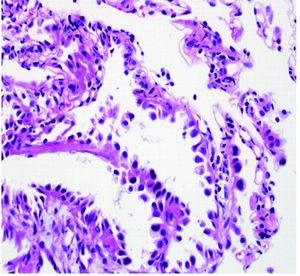

기도는 전도 기도와 가스 교환 기도로 나눌 수 있다. 가스 교환 기도는 폐포로 구성되는데, 폐포는 정상적인 호흡 동안 산소와 이산화탄소 교환을 담당하는 작은 공기 주머니이다. 폐포는 두 가지 유형의 세포로 구성된다. 제1형 폐포 세포는 폐포 표면의 95%를 덮고 재생될 수 없다. 제2형 폐포 세포는 폐포 상피 내 세포의 60%를 구성하지만, 폐포 표면의 3%만을 구성한다.[14]폐 선암은 제2형 폐포 세포에서 기원하며, 정상적인 세포 조절과 회전율을 방해하는 연속적인 분자 변화를 겪으면서 단계적으로 진행된다. 비정형 선종성 과형성(AAH)은 폐선암의 전구 병변으로 간주된다. AAH 병변은 5mm 미만이며, 단일 또는 다발성일 수 있고 CT 영상에서 간유리 음영을 보인다. AAH는 더 많은 유전자 돌연변이와 정상 세포 신호 전달 경로의 조절 장애가 축적됨에 따라 상피내 선암종(AIS)으로 진행될 수 있다. AIS 병변은 3cm 미만의 작은 종양으로, 기질, 흉막 또는 혈관으로의 침윤 없이 폐포 공간에 국한된 비정상적인 제2형 폐포 세포 성장을 보인다. 이러한 유형의 성장을 "lepidic"이라고 하며, 폐 선암종의 초기 단계에서 나타난다.[14]

폐 선암종은 비소세포폐암(NSCLC)의 세 가지 주요 아형 중 하나이며, 편평 세포 암종 및 대세포 암종도 이에 포함된다.[14]역사적으로 폐 선암종 분류 방법에 대해 많은 논쟁이 있었고, 여러 차례 분류 체계가 개정되었다. 가장 최근에는 2011년에 국제 다학제 폐 선암종 분류(International Multidisciplinary Classification of Lung Adenocarcinoma)가 발표되었는데, 이는 이 특정 유형의 폐암을 더 정확하게 설명하기 위한 여러 조직의 합의를 나타낸다.[32] 현재 분류 체계는 예후를 더 잘 예측하고 치료 결정을 돕는 것을 목표로 한다.[13]

침윤성 폐 선암종은 다양한 아형과 변이의 혼합을 포함하며, 2011년 합의에서는 가장 우세한 세포 패턴을 기반으로 다음 다섯 가지 주요 아형을 제시한다.

이러한 아형의 세포 패턴은 예후와 관련이 있으며, 양호(레피딕)에서 중간(선방 및 유두), 불량(미세 유두 및 고형)까지 다양하다.[32]